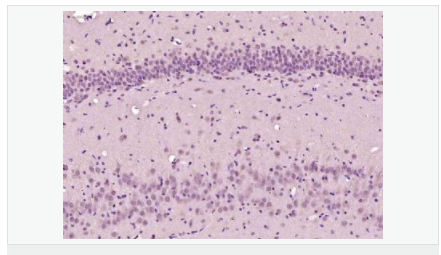

| 產(chǎn)品應(yīng)用 | ELISA=1:5000-10000 IHC-P=1:100-500 IHC-F=1:100-500 ICC=1:100-500 IF=1:100-500 (石蠟切片需做抗原修復(fù)) not yet tested in other applications. optimal dilutions/concentrations should be determined by the end user. |